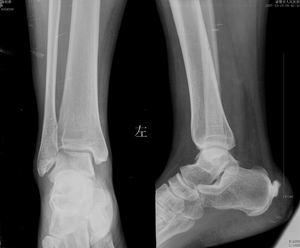

标题: CT10417:F36Y,跟骨跟腱附着处下方骨质密度影,请会诊. [打印本页]

标题: CT10417:F36Y,跟骨跟腱附着处下方骨质密度影,请会诊.

跟骨结节后部肿块半年,无明确外伤史,及红肿热痛.